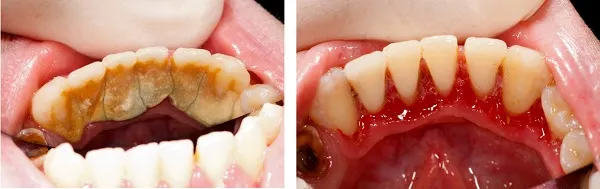

洗牙的專業術語是超聲波齦上潔治,是指用超聲波潔治器清除牙齦上方的牙結石、牙菌斑及色漬,並且對牙齒表面進行拋光,可以延緩牙菌斑和牙結石的再沈積。

洗牙是一種比較好的牙齒保健方法,是治療牙周病的基礎。定期洗牙不僅可以完全清除牙齒上的牙菌斑和牙結石,保持牙周組織健康,預防牙周病,還可以通過洗牙輕松發現細小的不易察覺的牙病,做到早發現、早治療的目的。因此為了預防和治療口腔疾病,減輕牙齦炎、牙周炎等,保持口腔衛生,每個人都應該定期洗牙。

02牙齦萎縮。長期積累的牙結石會壓迫牙齦,使牙齦紅腫、萎縮以及牙縫變大,進一步加重食物嵌塞。更容易導致鄰面齲。

03牙齒松動。牙齦炎進一步加重發展為牙周炎,牙槽骨吸收,牙根暴露,牙齒越來越松,直至脫落。

洗牙是一項重要的預防措施,同時也是早期口腔疾病的檢查和治療手段。牙結石一旦形成,單純的刷牙很難清除,必須由專業的醫生用專業的器械清除。除了每天正確的刷牙方法、飯後使用牙線,平時定期檢查牙齒,一般半年到一年需要洗一次牙。